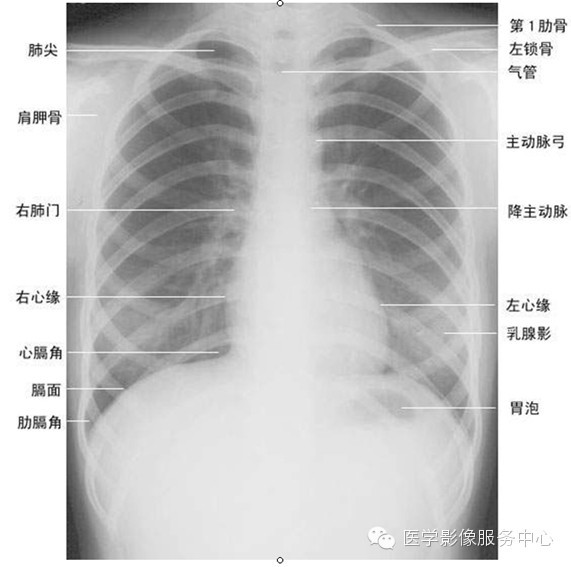

一张胸片能给我们提供多少信息?

超详细胸片读片入门攻略看完不信你还学不会

正常肺部胸片

正常肺部胸片正常人

肺部正常胸片影像图片

正常人的肺部胸片图